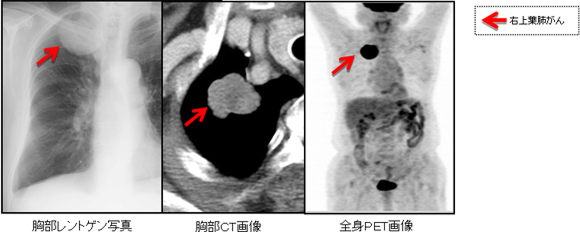

健康診断などの胸部レントゲン写真などで肺がんを疑わせるような陰影を指摘された場合は、外来通院で行える胸部コンピューター断層(胸部CT)検査や全身ポジトロンエミッション断層(全身PET)検査、頭部核磁気共鳴画像(頭部MRI)検査を行います。肺のできもの(腫瘍)の大きさ・形と肺以外の臓器(リンパ節、脳、骨、肝臓)の様子をみて、“肺がんかどうか”や他の臓器への転移の有無を診断します。これらの画像で肺がんが強く疑われると最終的な検査が必要になります。典型的肺がん症例の胸部レントゲン写真、胸部CT画像、全身PET画像を(図4)に示しました。

図4 右上葉肺がんの各種画像検査